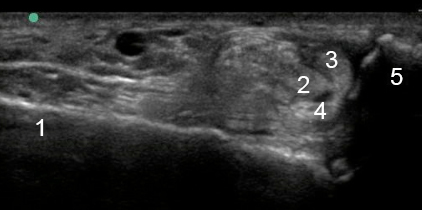

Image - Cheville latérale : Rupture du tendon fibulaire

1. Calcanéus

2. Long fibulaire

3. Tendon court péronier

4. Tendon court péronier

5. Malléole latérale